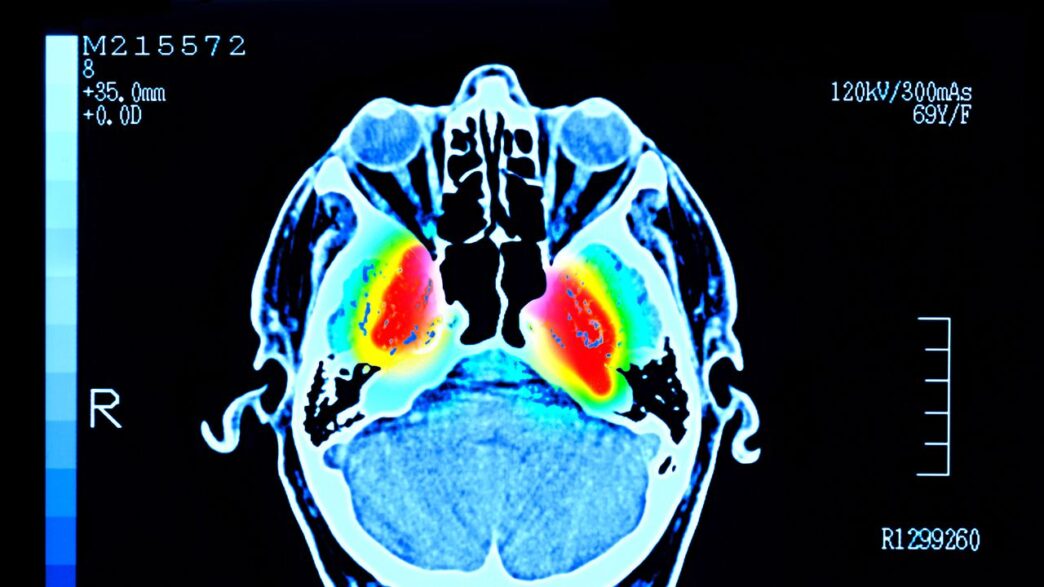

La enfermedad de Parkinson es una afección cerebral que empeora con el tiempo. Tiene su origen en la pérdida de neuronas productoras de dopamina, lo que altera la comunicación en los circuitos del cerebro que controlan el movimiento. El síntoma más conocido son los temblores involuntarios, pero también hay rigidez, lentitud de movimientos y problemas de equilibrio, además de manifestaciones no motoras como alteraciones del sueño, depresión o deterioro cognitivo.

Aunque el Parkinson no tiene cura, un mejor entendimiento de las causas que detonan la pérdida de neuronas dopaminérgicas podría desembocar en mejores tratamientos preventivos. Sin embargo, tampoco está claro qué desencadena ese deterioro, ni por qué ciertas neuronas (como las de una región del cerebro llamada sustancia negra, SNc) se ven más afectadas que otras (como las de la región del área tegmental ventral, VTA).

Aunque las neuronas en cuerpos celulares todavía estaban mayormente intactas en ese periodo (tanto en la SNc como en la VTA), la pérdida de axones ya era notable desde la primera semana. Una vez transcurrido el mes (cuatro semanas), comenzó a observarse muerte neuronal en los cuerpos celulares. Las neuronas de la SNc fueron mucho más vulnerables al daño que las de la VTA. Además, las fibras que conectan la SNc con el estriado dorsal fueron las primeras y más gravemente afectadas.